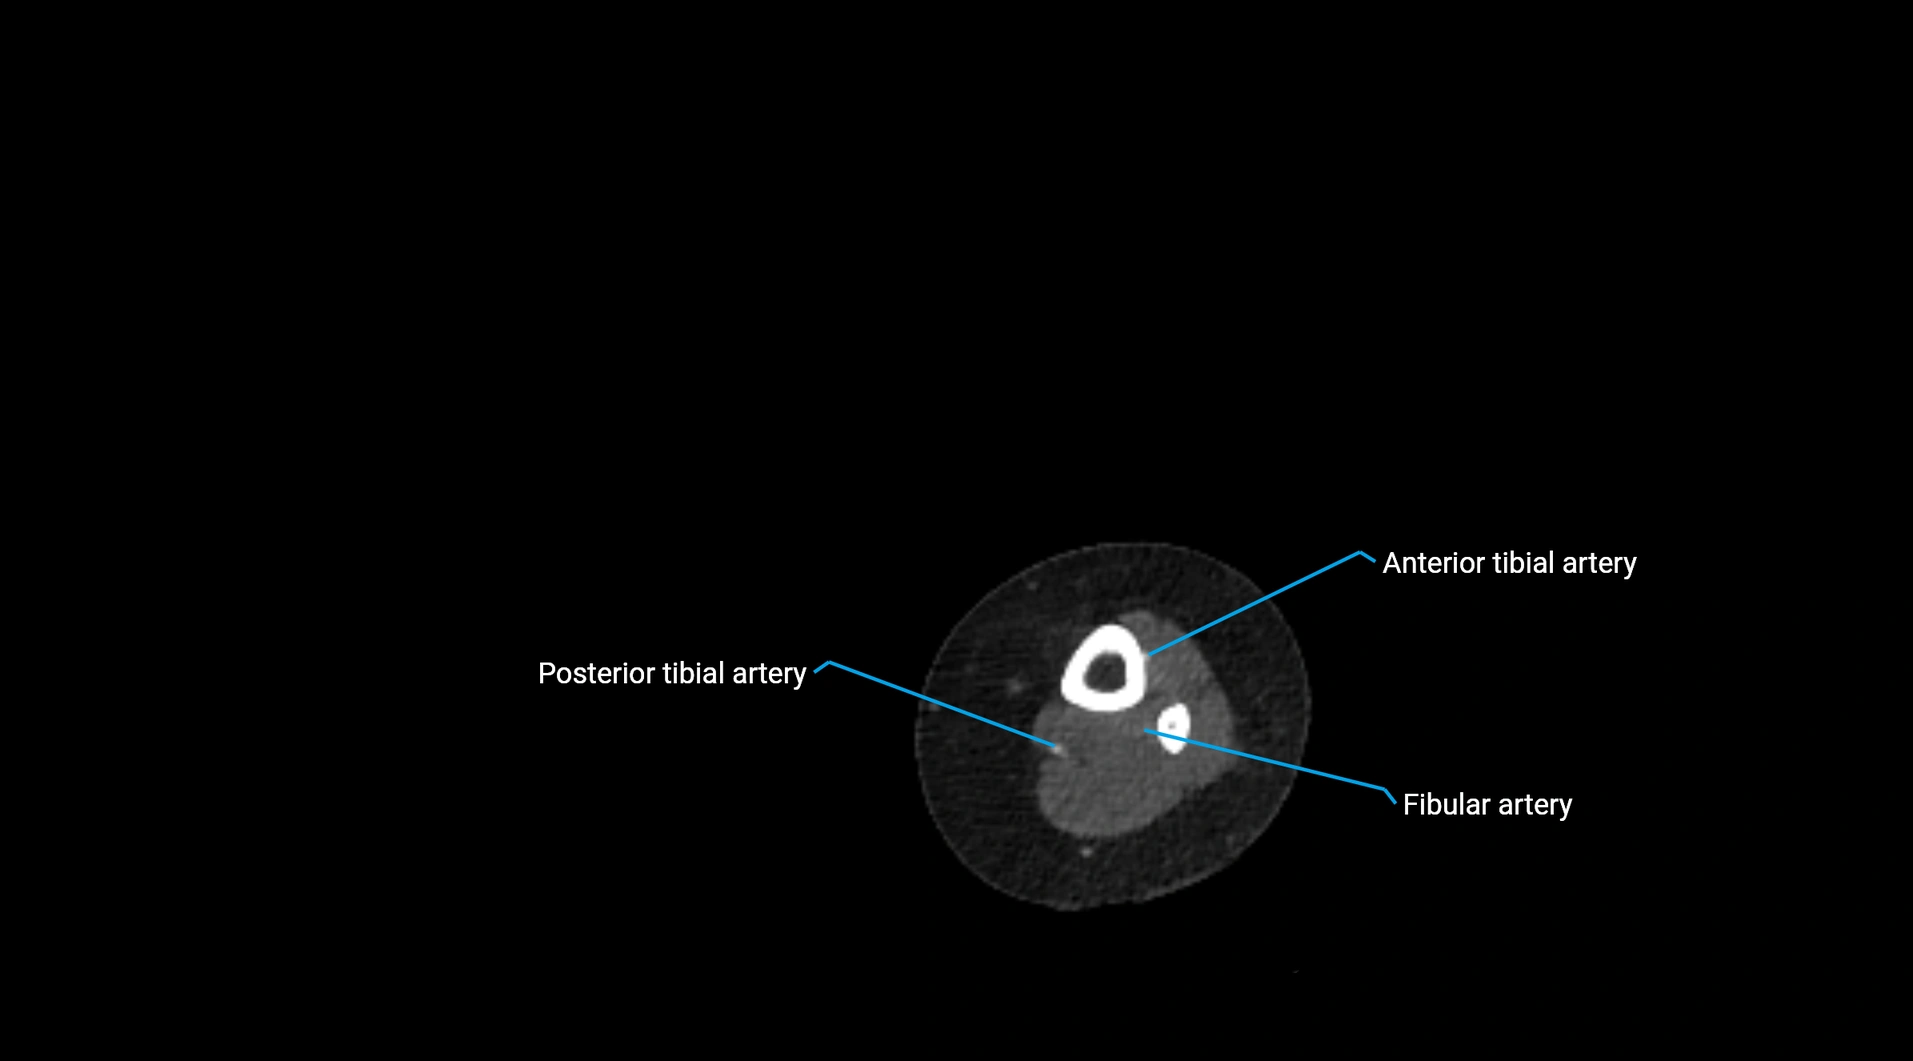

CT images

image